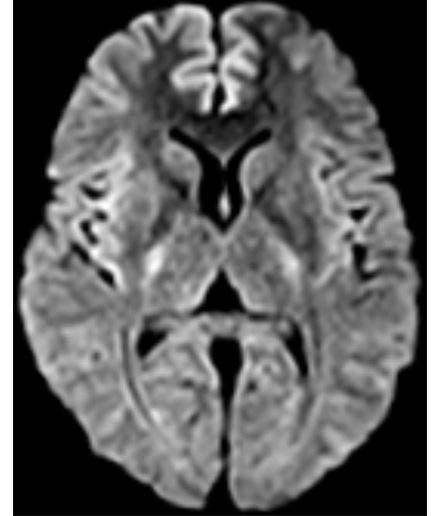

| 颅脑-DWI |